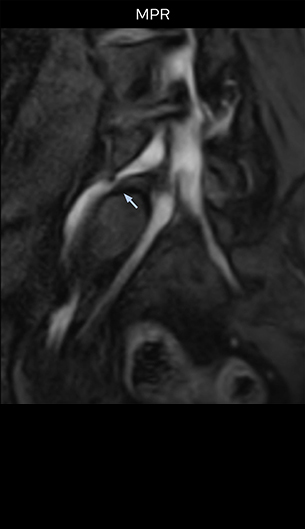

Good spatial resolution is required

“For both brachial and lumbar plexus, we are currently using a 230 mm FOV and voxels of about 1 x 1 x 2 mm acquired (1 x 1 x 1 mm reconstructed). This provides us a good representation of the nerves, even though this FOV is relatively small. Regarding the inplane resolution, we hope to be able to bring that down to 0.7 mm, similar to our typical 2D multislice T2W images,” says Tanji.

“Recently, the two surgical methods extreme and oblique lateral interbody fusion (XLIF and OLIF) have become mainstream for minimally invasive treatment of lumbar spinal canal stenosis and intervertebral foramen stenosis. With these surgical techniques, the spine is approached from the flank, and prior knowledge of the exact anatomy of the lumbosacral plexus would be extremely helpful. To that end, high slice resolution (less than 1 mm acquisition) that enables sharper sagittal MPR images will be needed.”